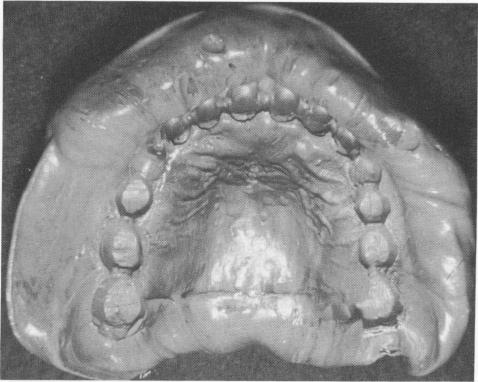

A master stone model with three duplicate implant shafts was prepared (Fig. 10-233), and a scalloped gold template was fabricated from the stone cast. The template included vertical extensions anteriorly, an improvement that eliminates the need for the gold coping connecting bar shown in the previous cases, and mushroom-shaped protrusions in the triplant areas for inclusion in the acrylic cores. These help bind the triplants to the template. Holes were then made between the mushroom-shaped protrusions to accommodate the triplant pins (Fig. 10-234). These holes were determined by taking radio-graphs while the template was in the mouth.